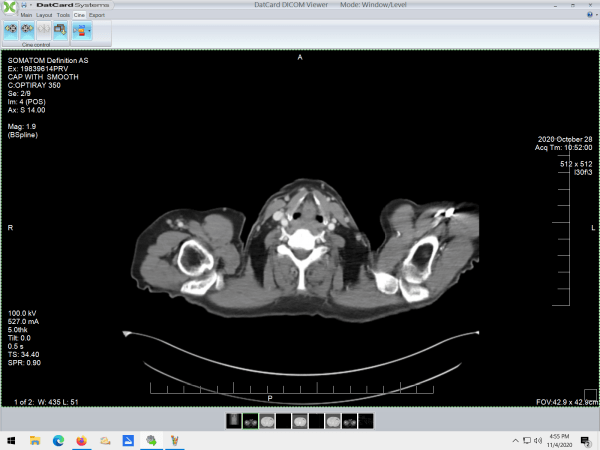

I had a CT scan last week. Just for the heck of it I asked if I could get a copy of the .dcm files and they burned me a DVD that included viewing software. Pure awesome.

I opened the program, fumbled around a bit, and found that I have a little happy dude living right under my chin.

In another file, there were soft-tissue images, and the little happy dude showed up there, too.

The scan turned up nothing significant. That made me VERY happy.